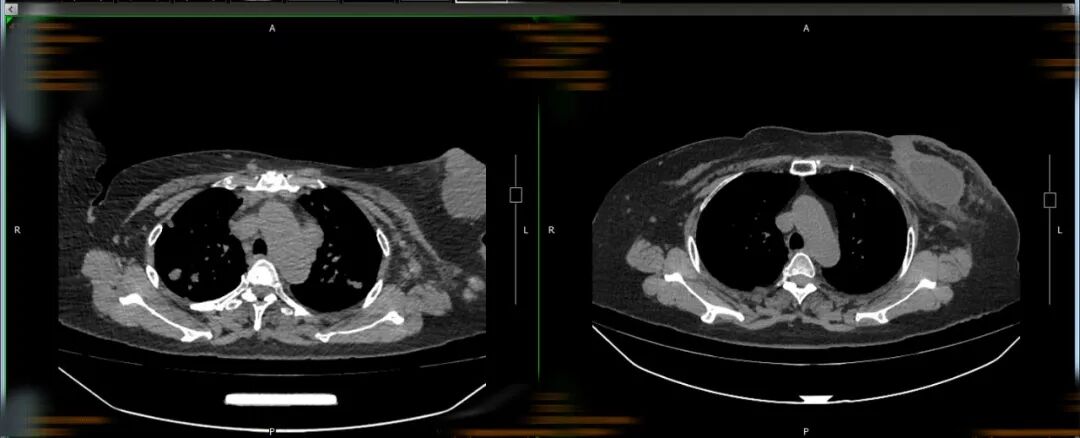

王婆婆2022年7月2日入院

与2023年7月19日肺部CT对比